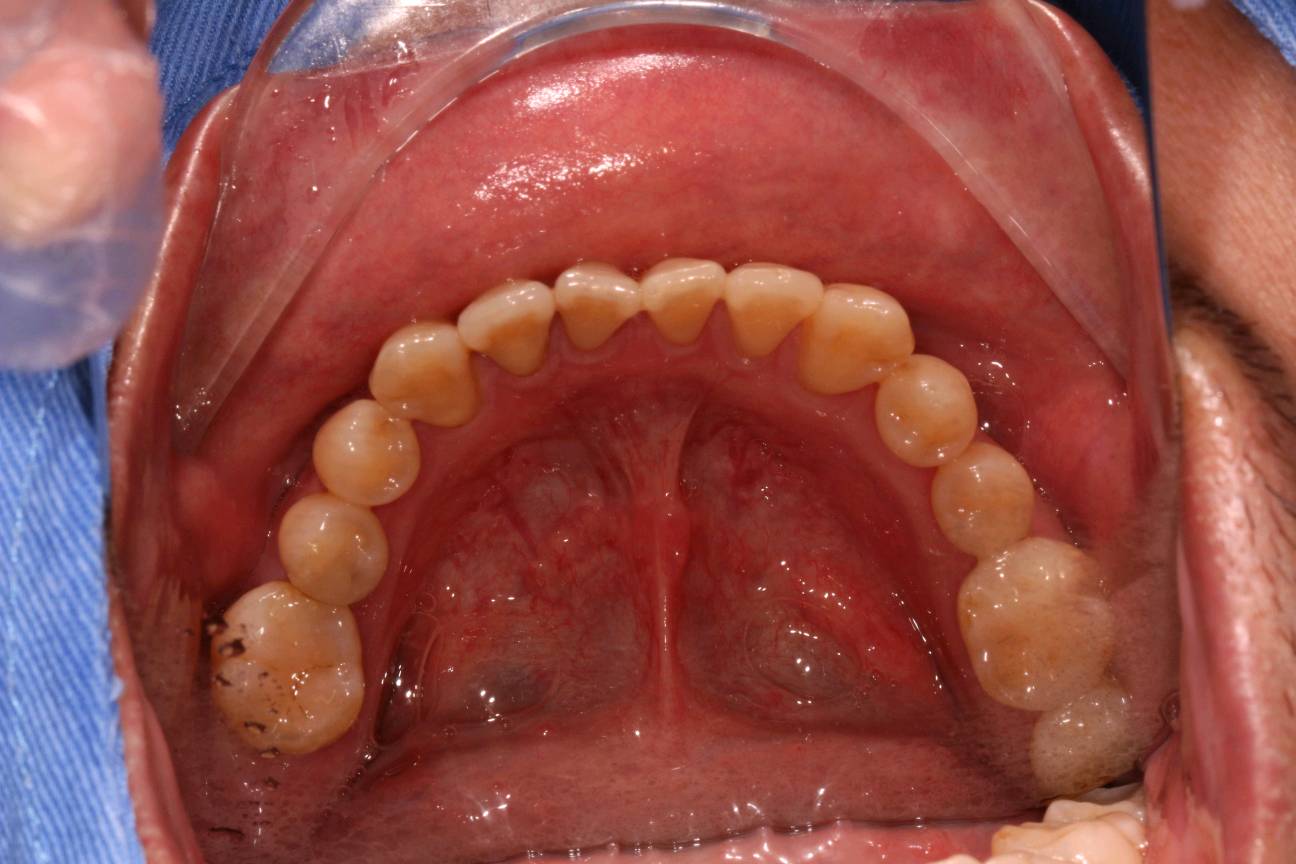

患者男,35岁,右下后牙缺失半年。口内检查:47牙体缺失,缺牙区牙槽嵴中度萎缩,无骨尖。颌龈距离约5mm。46松动+++,牙龈中重度退缩。X线示缺牙区骨密度良好。46牙槽骨吸收至根尖1/3。

术前